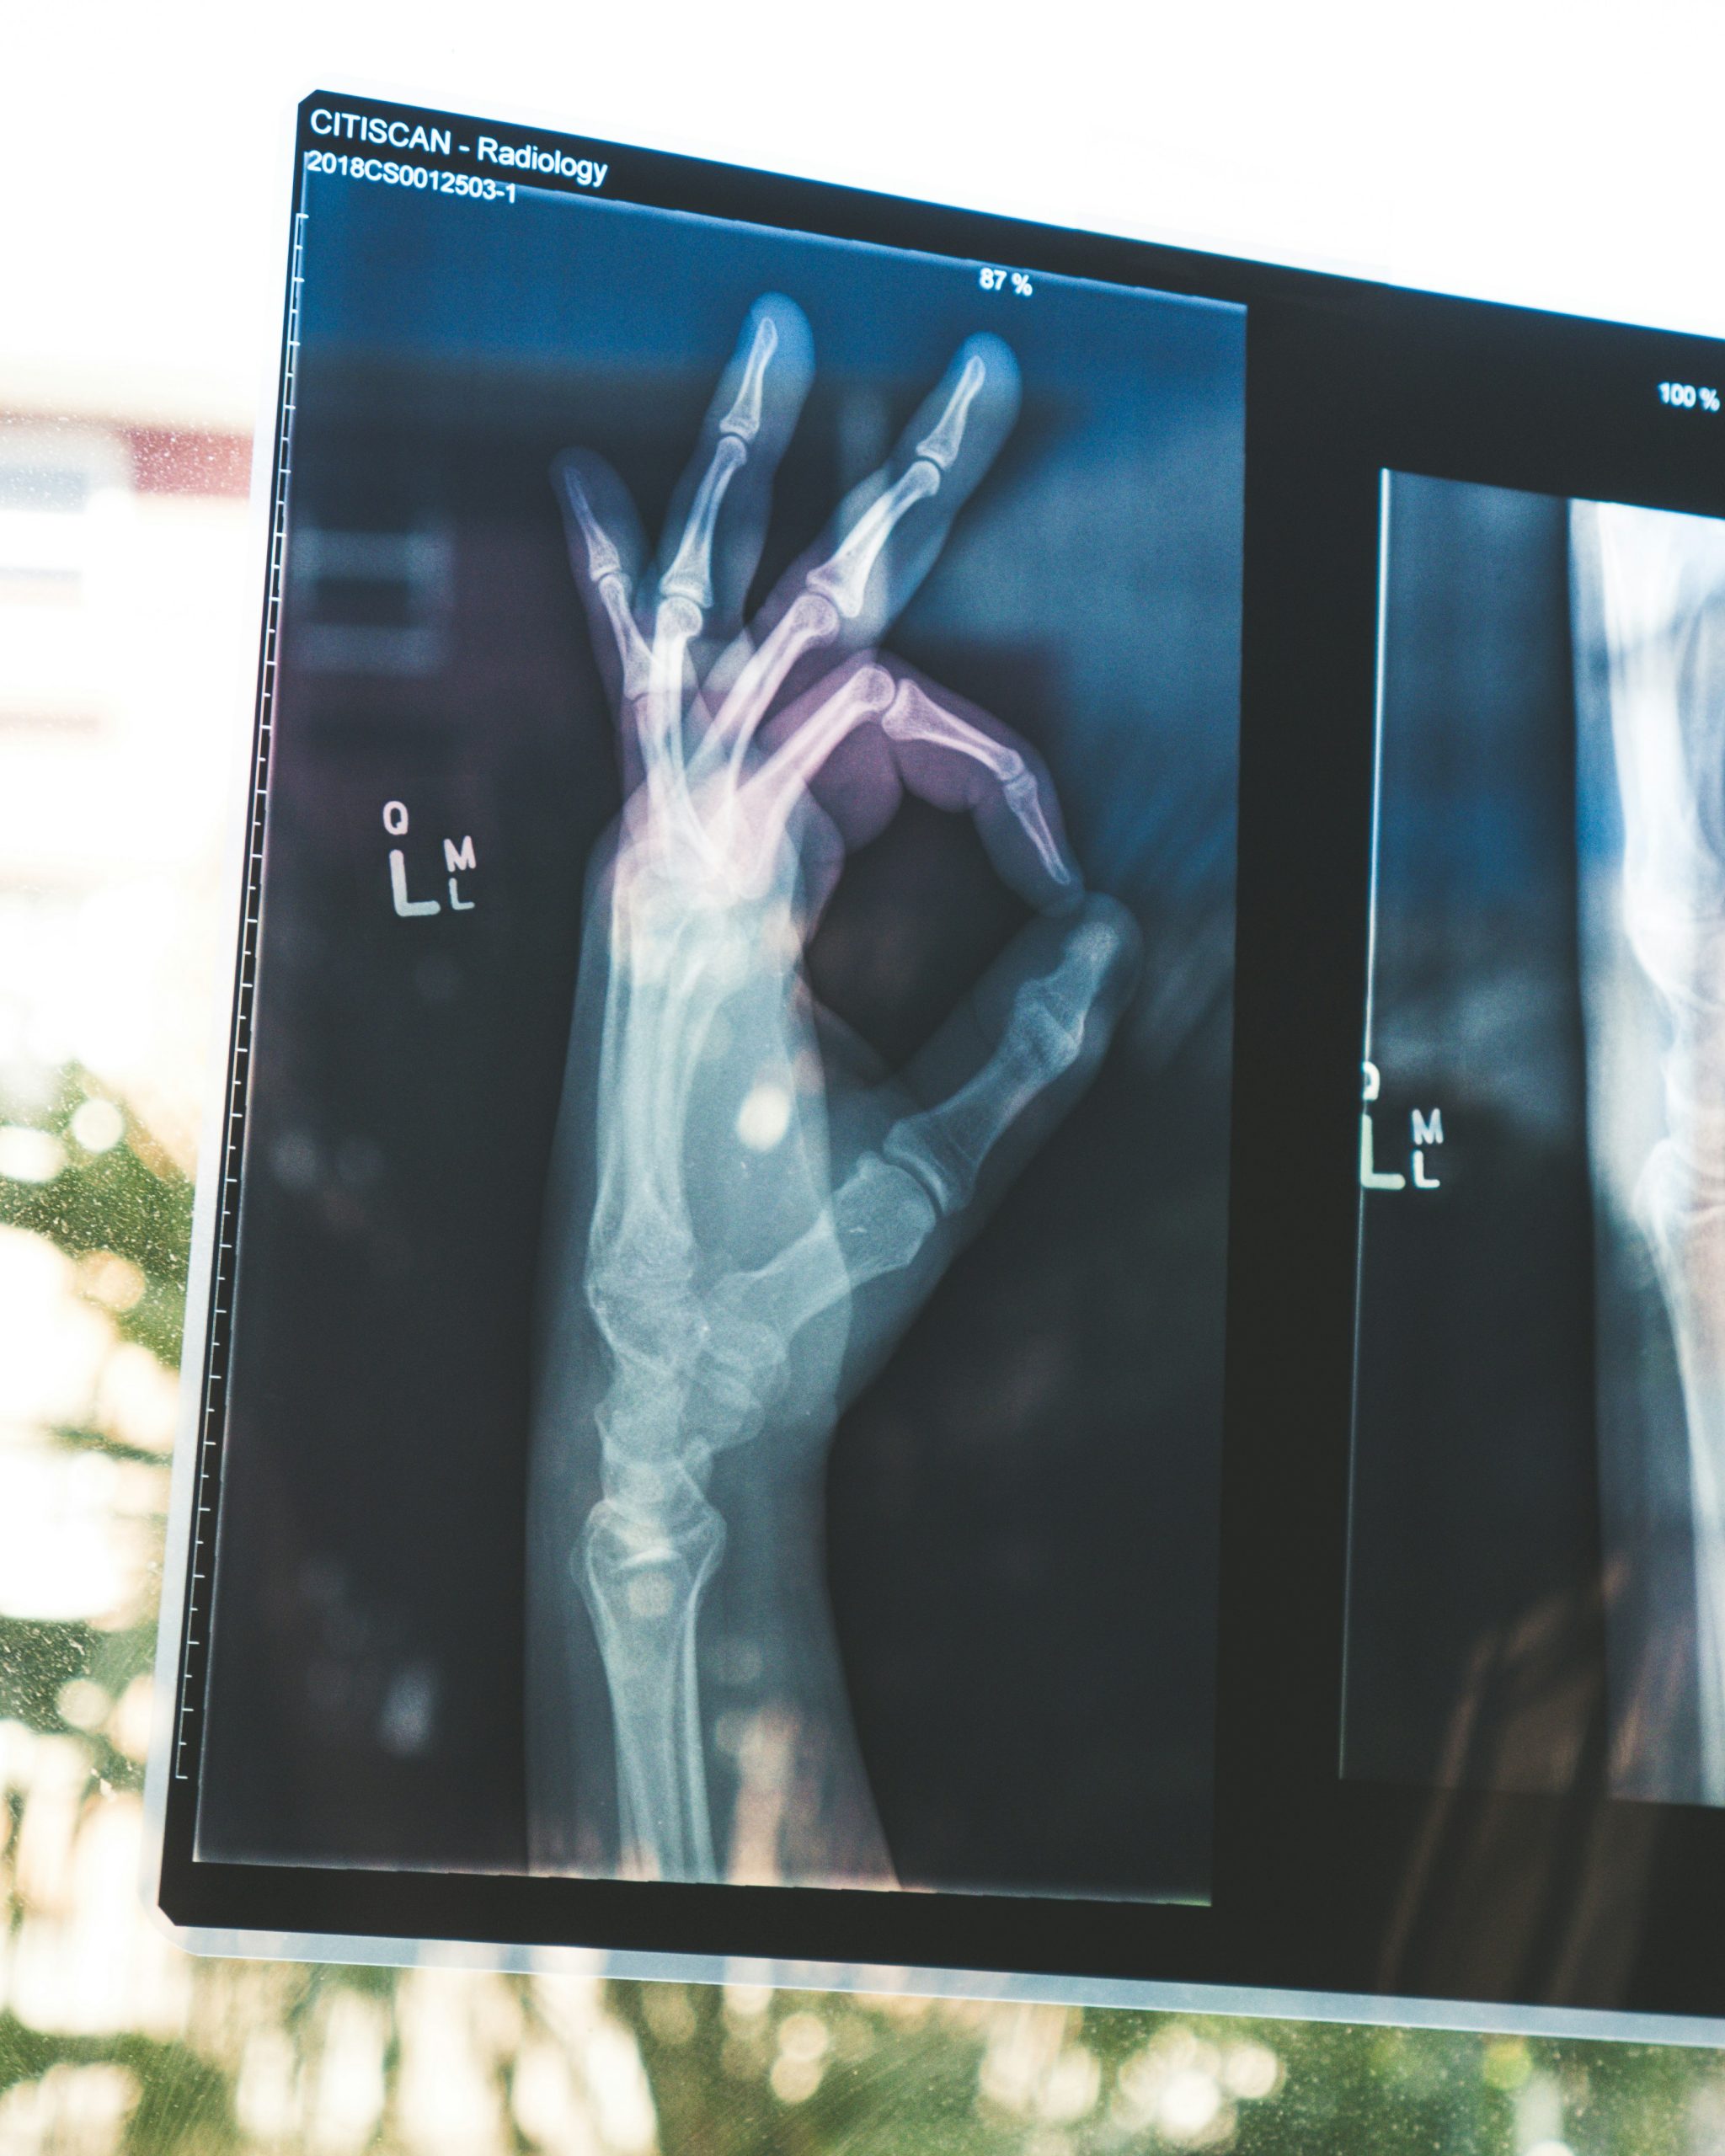

The first step to REGENactive therapy is the Health Risk Assessment screening, which is already being implemented in Dhaka. Mayfair Wellness Clinic in Gulshan recently announced its new AI-assisted holographic health analyzer which requires the patient to input their accurate age, height and weight measurements and to place their hands on a panel to allow the machine to perform a full-body scan, after which a detailed report is generated, providing a complete picture of the user’s health. This is a quick, painless, and ultimately cost-effective option for those merely looking for a health checkup, although it must be noted that in case of an active infection, it is still better to go to a human phlebotomist for tests.